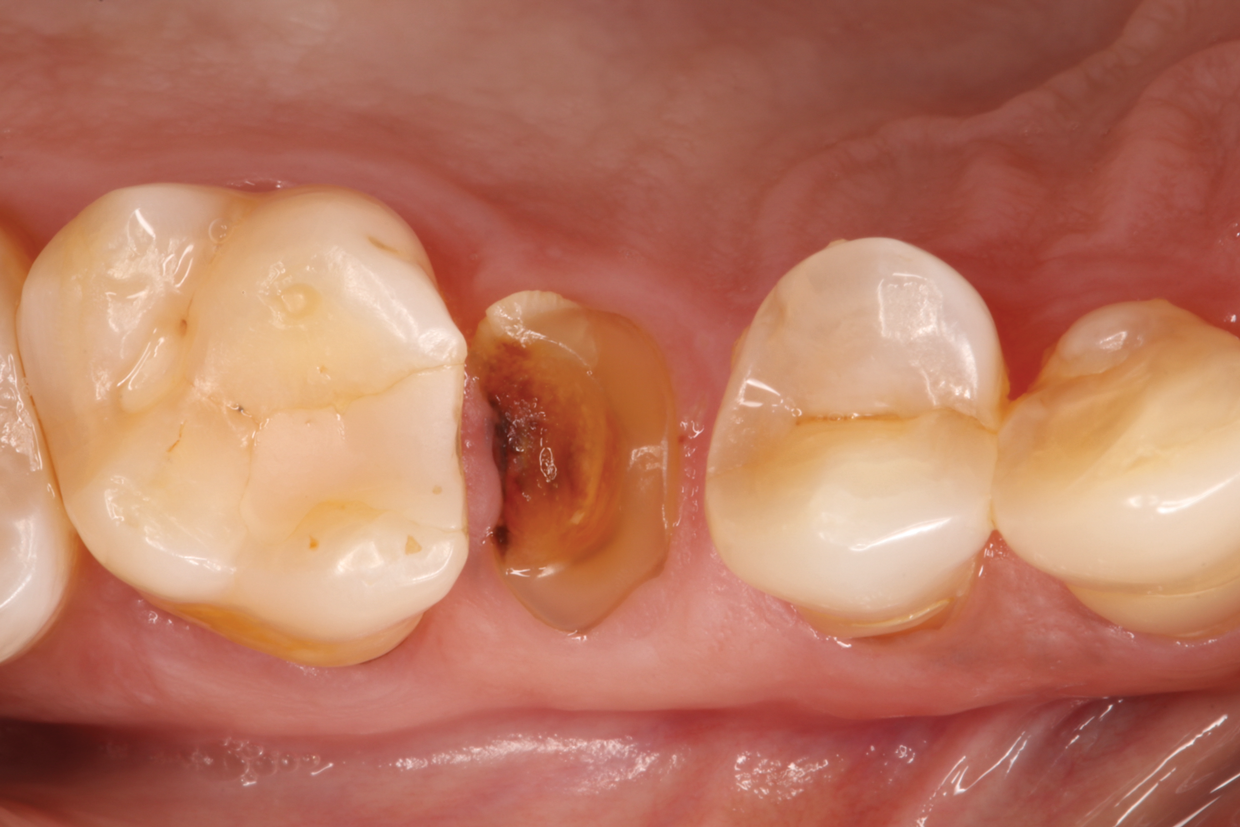

Fig 1. Hopeless maxillary second premolar.

Figure 1

In the case presented, a 56-year-old male patient had a coronal fracture on tooth No. 13, which was deemed hopeless (Figure 1). Treatment options were discussed with the patient, including endodontic therapy followed by surgical crown lengthening with forced tooth eruption to expose sound tooth structure for prosthetic tooth reconstruction. Due to the short length of the residual root, however, an unfavorable prognosis was assigned to this treatment option. The clinician determined, therefore, that replacement of the tooth with a dental implant would be the most conservative, viable, and predictable option for tooth replacement since significant tooth reduction of unrestored adjacent teeth would be necessary for three-unit fixed-bridge fabrication and the patient did not accept any removable replacement options.